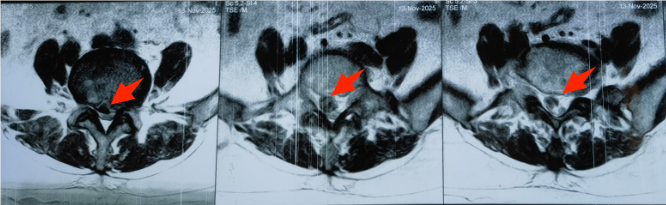

敦化市的赵女士半年前突发右下肢疼痛,短期内迅速加重为右小腿持续性剧痛、足背麻木及踝关节背伸无力,夜间难以入眠,口服止痛药无效,日常行走受限。经当地医院腰椎MRI检查,确诊为“L4-L5腰椎间盘突出症(脱垂游离型)”,突出的椎间盘组织已脱离椎间隙坠入椎管,对右侧L5神经根形成重度压迫。具备明确手术指征,但因游离组织位置深、与神经根粘连紧密且年龄偏大,手术风险和难度较高,当地医院建议转至上级医院接受专业治疗。

患者经当地医疗机构推荐至吉林省一汽总医院,骨科滕宇飞主任团队接诊后,立即对赵女士进行全面评估,明确手术核心诉求:精准摘除游离组织、解除神经压迫并保护脊柱稳定性。考虑到手术复杂性,团队预判了髓核定位难、粘连分离易损伤神经等技术挑战,特邀吉林大学中日联谊医院尹飞副主任跨院会诊。两位专家结合影像学资料与患者情况,反复研讨后确定“腰椎管减压+游离髓核摘除+椎弓根螺钉固定植骨融合”方案,兼顾减压效果与脊柱稳定性,降低复发风险。